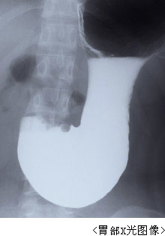

X光检查

X光检查是通过服用钡液进行x光拍照的一种检查方法,而用于胃的检查一般分为间接x光检查和直接x光检查。间接x光检查是以发现病变体为首要目标的检查方法,从时间、经济、患者负担等角度考虑,一般被用于集体检查等场合。但是由于该方式使用小号的底片程序化的检查方法,对于较小的胃癌以及部分中晚期胃癌有疏漏的可能,近些年,选择胃镜检查的越来越多。而直接x光检查是在精密检查过程中的一种检查方法。其还可以被分为通过调整两种造影剂量进行的双重造影法和通过压迫以及改变体位及方向的摄影的方法。直接x光的方法可用于鉴别肿瘤良性恶性、病灶状况、浸润范围、及浸润深度。